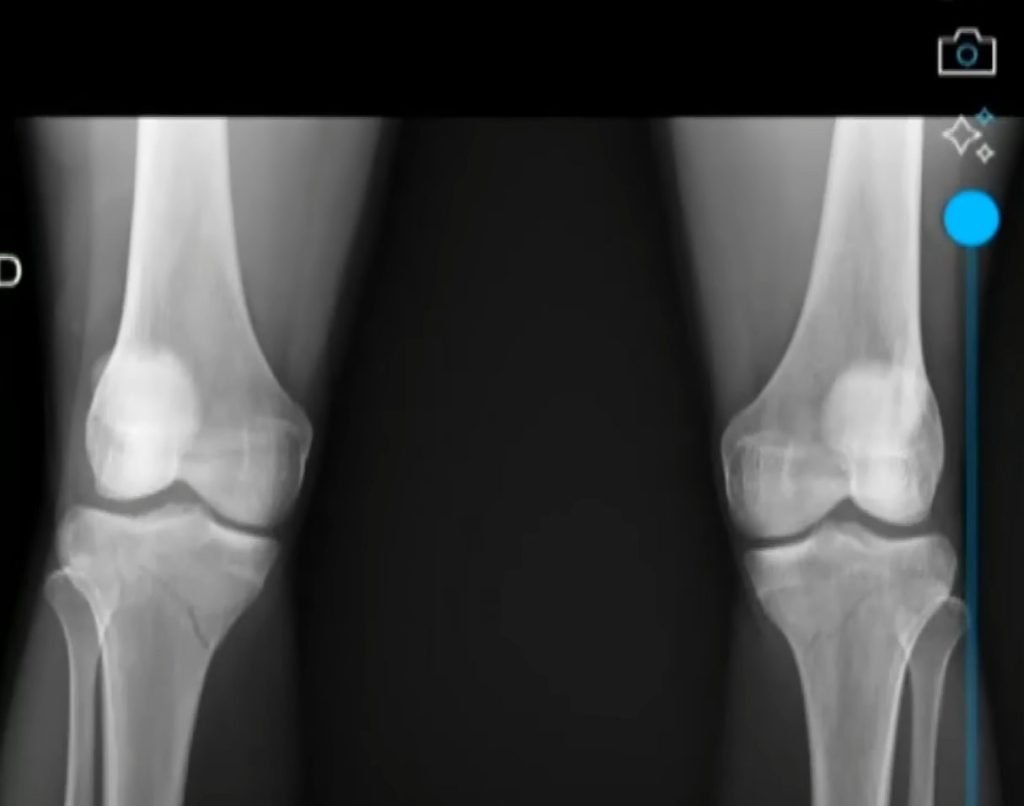

The victim, identified as Júlia Stefany Cotrim Beserra, sustained fractures to both knees, leaving her unable to walk for several months following the incident.

She was later admitted to Hospital de Base, where she underwent surgery on April 14.

Doctors have reportedly advised that she will be unable to walk for months and must avoid physical activity for at least one year as she recovers from her injuries.